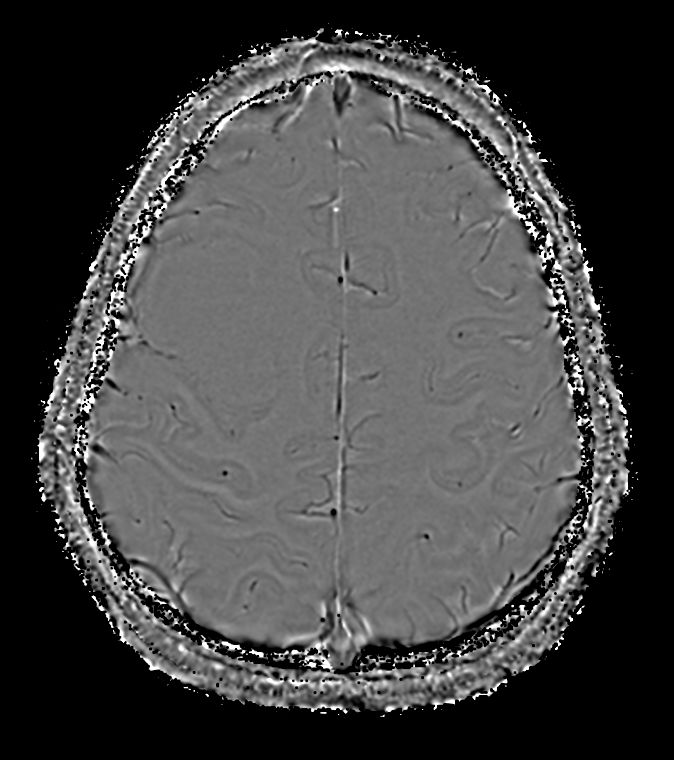

SWIp (Modulus) Compressed SENSE

-

SWIp (Phase) Compressed SENSE